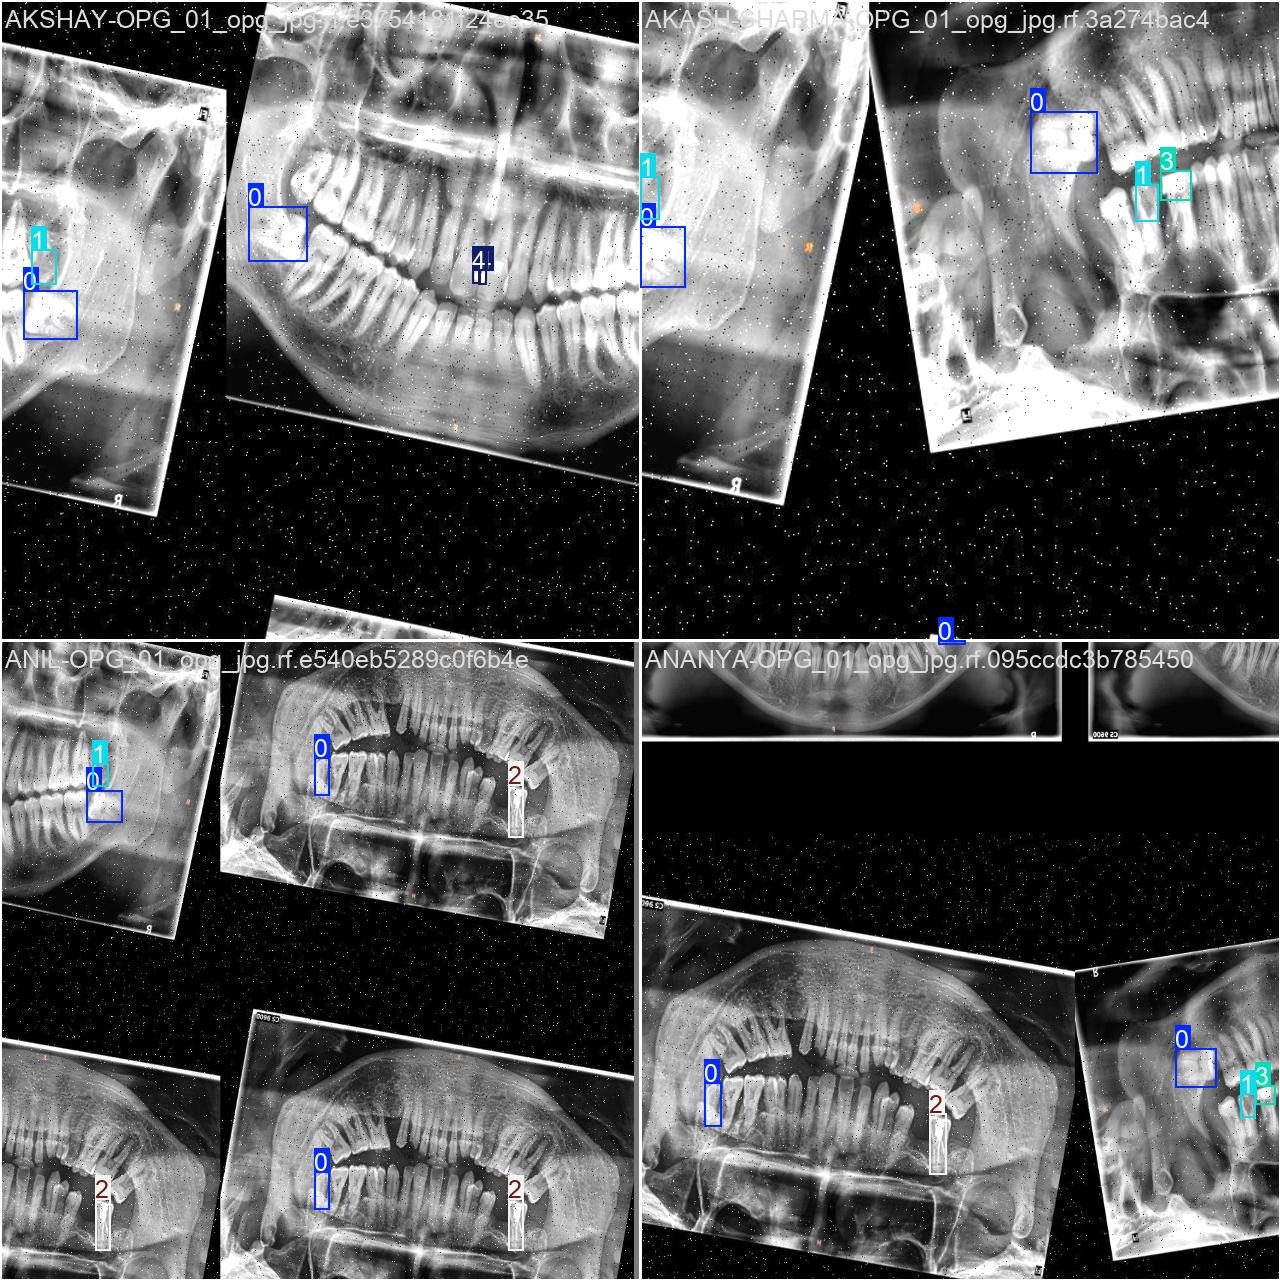

2.数据集准备与训练

本研究使用了包含口腔牙齿CT影像的数据集,并通过Labelimg标注工具对每张图像中的目标边框(Bounding Box)及其类别进行标注。然后主要基于YOLOv8n这种模型进行模型的训练,训练完成后对模型在验证集上的表现进行全面的性能评估及对比分析。模型训练和评估流程基本一致,包括:数据集准备、模型训练、模型评估。本次标注的目标类别为口腔牙齿CT影像,数据集中共计包含4647张图像,其中训练集占3684张,验证集占963张。部分图像如下图所示:

部分标注如下图所示: